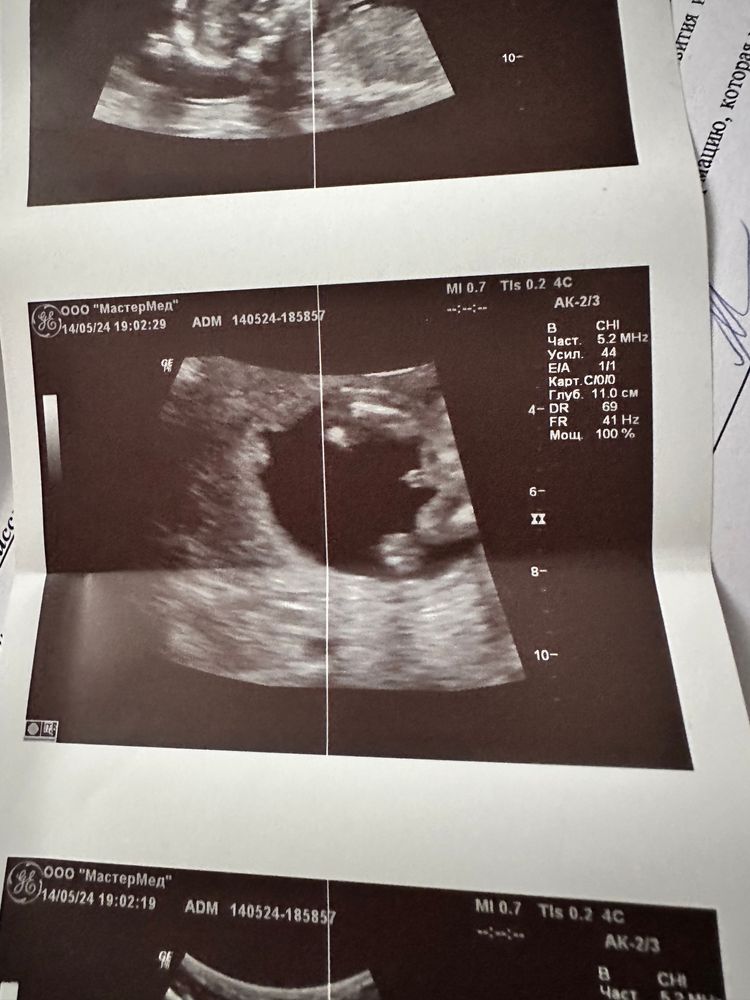

Изображение

Natali Kitten, тут явно мальчик